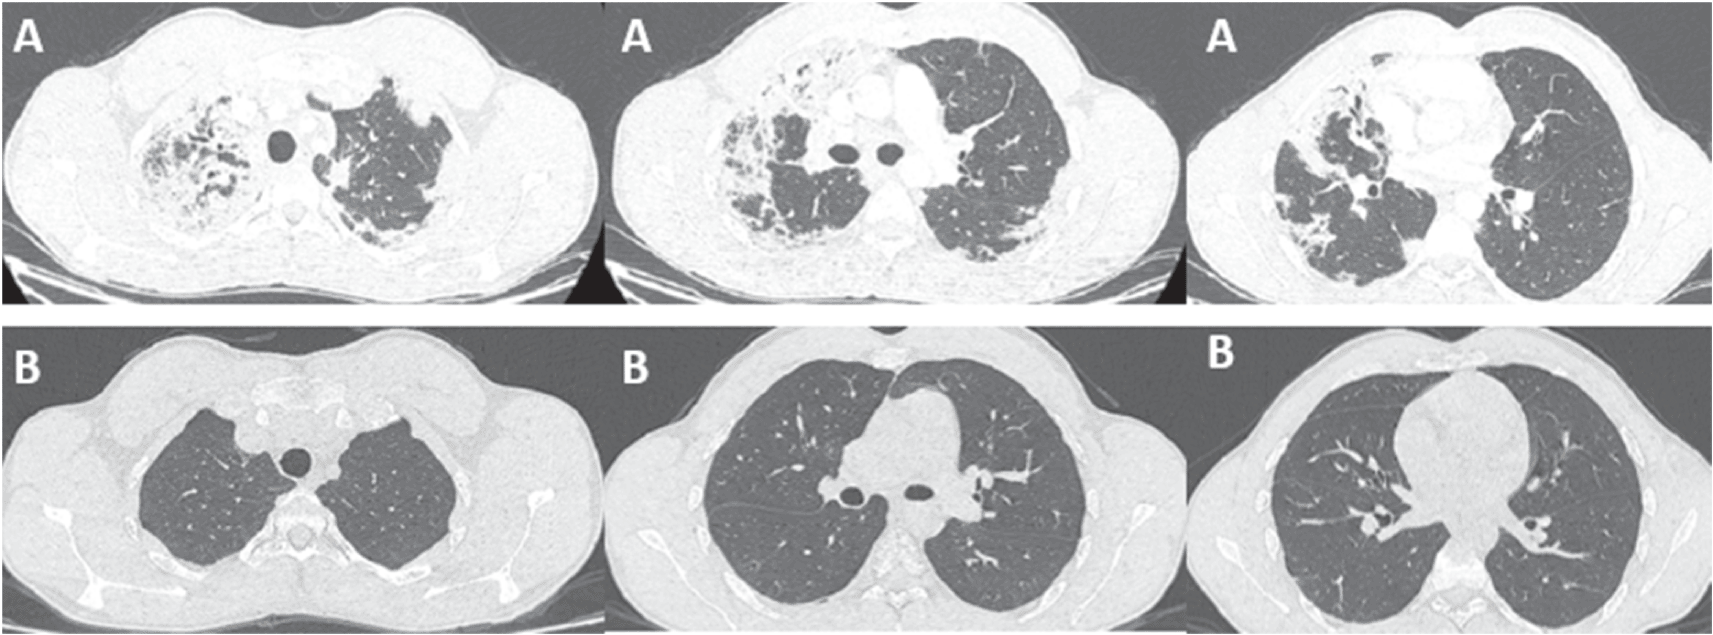

A 21-year-old patient, high-level athlete, was admitted for dry cough and progressively worsening dyspnea for a month. He also reported 10 kg weight loss during this period. He did not have high fever or wheezing. He was a never smoker and he had no previous medical history. Laboratory findings showed an elevated leukocyte count with a high level of eosinophilia (4.57 G/L, 34.7%). Liver and kidney function tests were normal. Chest computed tomography (CT) showed bilateral and peripheral infiltrative shadows, essentially on the right side (Figure 1). Bronchoalveolar lavage fluid (BALF) showed an elevated eosinophil percentage (26%). Antineutrophil cytoplasmic antibodies (ANCA) were negative. FIP1L1-PDGFRA and JAK2 V617F mutations were absent. Video-assisted thoracoscopic lung biopsy showed pulmonary eosinophilia with appearances of organizing pneumonia (Figure 2). The diagnosis of ICEP was established. The patient was managed with high-dose of corticosteroids (20 mg dexamethasone for three days, then 1 mg/kg/day of prednisolone which was tapered over six months). Clinical, biological and radiological improvements were noted. However, the patient relapsed three days after the treatment was stopped. He responded again to steroids. But because of the side effects he experienced from chronic steroid use (muscle wasting, tendon rupture and depression), the decision to initiate an off-label anti-IL5 treatment was made. A monthly 100mg of subcutaneous mepolizumab was started and oral corticosteroids were gradually stopped. With 12 months of hindsight, he was asymptomatic, the eosinophil counts dropped to normal range (Figure 3) with a complete radiological clearance. No adverse reaction to the therapy was noted.

Our second case is a-27-year-old man, active military, admitted for increasing dyspnea, cough and wheezing for a few weeks. He had been diagnosed with asthma one year earlier. He was an ex-smoker of two-five packs per year. Tests showed blood eosinophilia (2G/L, 15%). The C-reactive protein level was 10 mg/L. Chest CT revealed peripheral and diffuse ground glass opacities. The serum Immunoglobulin E level was 502 IU/mL. ANCA were negative. The BALF showed a marked percentage of eosinophils of 31%. Further investigations were unrevealing for parasitic or fungus infections, and hematologic disorders. Hence, the diagnosis of ICEP was made. Systemic corticosteroids were prescribed (4 days of 20 mg of dexamethasone, then 1 mg/kg/day of prednisone, which was tapered over 3 months). His asthma was treated with daily inhaled budesonide and formoterol. The patient responded well to the therapy: a rapid resolution of symptoms was noted, the eosinophils blood count dropped to normal range, and the pulmonary infiltrates completely disappeared. However, attempts at tapering the corticosteroids below 35 mg were met with three relapses in 16 months, which were associated with clinical worsening, reascension of eosinophil count, recurrence of pulmonary lesions and multiple hospital admissions. A high glucose level due to the chronic steroid use was noted. Subcutaneous mepolizumab 100 mg monthly was initiated. A gradual decrease of oral steroids was well tolerated (Figure 3). The patient is currently at four months of overlap of anti-IL5 and tapering doses of corticosteroids. With a current dose of 20 mg of prednisone, no relapse has occurred.